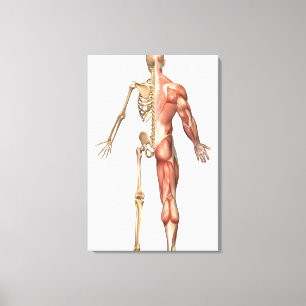

Impressão Em Tela Músculos Das Costas E Do Pescoço

Preço107,00 €

Poster O Esqueleto Humano E O Sistema Muscular,

Preço36,25 €